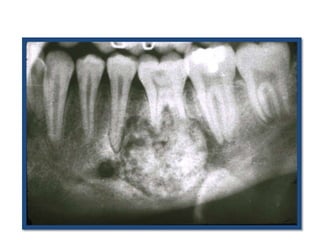

Honeycomb-like small

ameloblastoma at early stage with

evidence of root resorption.